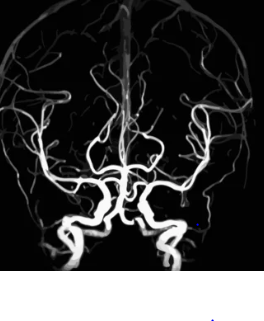

뇌출혈이 의심되는 경우, 즉시 의료 기관을 방문하여 정밀 진단을 받는 것이 중요합니다. 컴퓨터 단층촬영(CT)이나 자기공명영상(MRI) 검사를 통해 뇌 내부의 출혈 여부를 확인할 수 있으며, 필요한 경우 적절한 치료를 받을 수 있습니다.